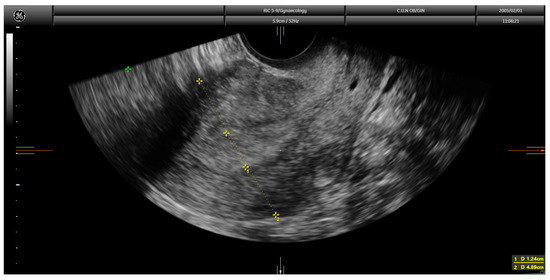

Current guidelines recommend the assessment of myometrial infiltration by magnetic resonance imaging or transvaginal ultrasound in the pre-operative work-up of women with endometrial cancer [4]. Both techniques offer similar diagnostic performance [5]. However, expertise is clearly needed when ultrasound is used [4]. Myometrial infiltration assessment by transvaginal ultrasound can be conducted using several approaches, namely examiner’s subjective impression, Karlsson’s method and Gordon’s method [6]. When using the examiner’s subjective impression, the depth of myometrial infiltration is estimated by assessing the point at which the myometrium–endometrium interface is not identified clearly and then by assessing the supposedly tumor-free myometrial wall at this point. The opposite myometrial wall is used for comparison, and, if marked asymmetry is found, deep (≥50%) infiltration is assigned; if myometrial thickness was similar in both myometrial walls, superficial (<50%) infiltration is assigned. In the Gordon’s approach, the ratio of the distance between the maximum tumor depth and total myometrial thickness is estimated. If the ratio is <50%, myometrial invasion is estimated as less than half of the myometrium; in contrast, if the ratio is >50%, it is classified as more than half of the myometrium (Figure 1).

Figure 1. Transvaginal ultrasound showing a case of superficial infiltration in endometrial cancer using the Gordon’s method. The ratio of endometrial thickness/uterine anteroposterior diameter was 33.4%.